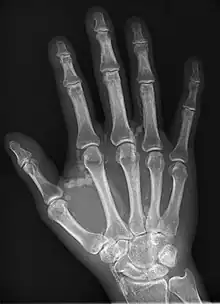

| Hand radiograph showing tumoral calcinosis, PA radiograph of the right hand showing tumoral calcinosis-like metastatic calcification in a patient on dialysis. Dialysis alters calcium phosphate product (>70). Idiopathic tumoral calcinosis is autosomal dominant and is not associated with dialysis. Note the premature arterial calcification which is a clue that this is a renal patient. Vascular calcification contributes to an increase in morbidity. |

Tumoral calcinosis is a rare condition in which there is calcium deposition in the soft tissue in periarticular location, around joints, outside the joint capsule.[1] They are frequently (0.5–3%) seen in patients undergoing renal dialysis. Clinically also known as hyperphosphatemic familial tumoral calcinosis (HFTC), is often caused by genetic mutations in genes that regulate phosphate physiology in the body (leading to too much phosphate (hyperphosphatemia)). Best described genes that harbour mutations in humans are FGF-23,[2] Klotho (KL),[3] or GALNT3.[4] A zebrafish animal model with reduced GALNT3 expression also showed HFTC-like phenotype,[5] indicating an evolutionary conserved mechanism that is involved in developing tumoral calcinosis.